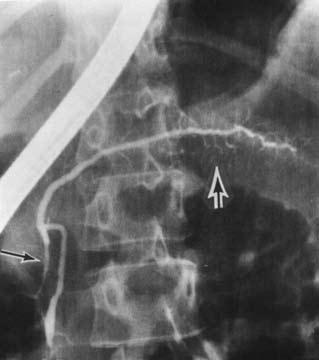

Ретроградная холангиопанкреатикография (РХПГ), позволяющая контрастировать вирсунгов проток, выполняется в ходе эндоскопического исследования (подробнее см. ниже) (рис. 132).

Рис. 132. Ретроградная панкреатикография при хроническом панкреатите. На снимке виден резко расширенный главный панкреатический проток

На рентгенограмме могут быть обнаружены характерные для ХП признаки: расширение главного панкреатического протока иногда в виде контрастной «цепи озер», наличие в протоке стриктур, конкрементов, а также сообщающихся с протоком полостей (псевдокист). На одновременно осуществляемой холангиограмме может выявляться стриктура терминальной части холедоха, расширение вне‑и внутрипеченочных желчных протоков, холедохолитиаз и т. д. Учитывая возможные осложнения РХПГ (острый панкреатит, острый холангит вплоть до развития бактериально‑септического шока при наличии инфекции в протоках до РХПГ), это исследование выполняется в основном по абсолютным показаниям, перед операцией или с одновременной эндоскопической декомпрессией протоков.